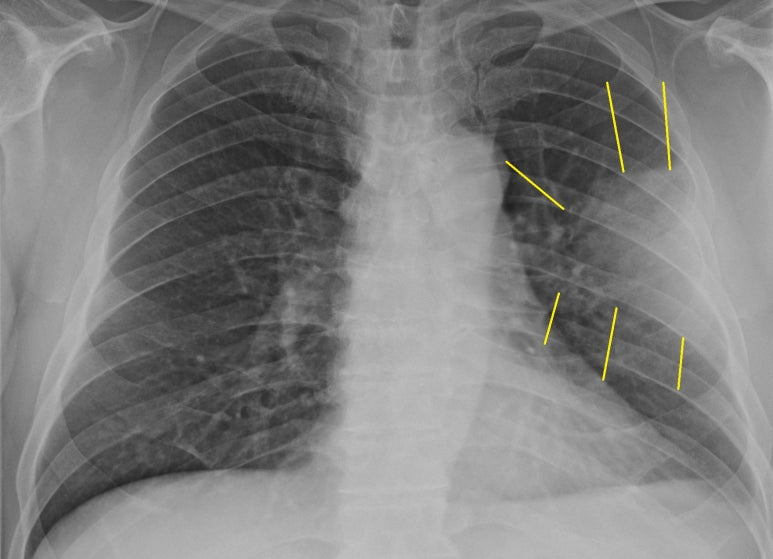

검진용 흉부촬영 1매를 시행하고, 아래 모습을 보자마자

검진은 중지

측면사진 추가로 촬영하고 폐렴에 대한 평가 및 투약 시작함